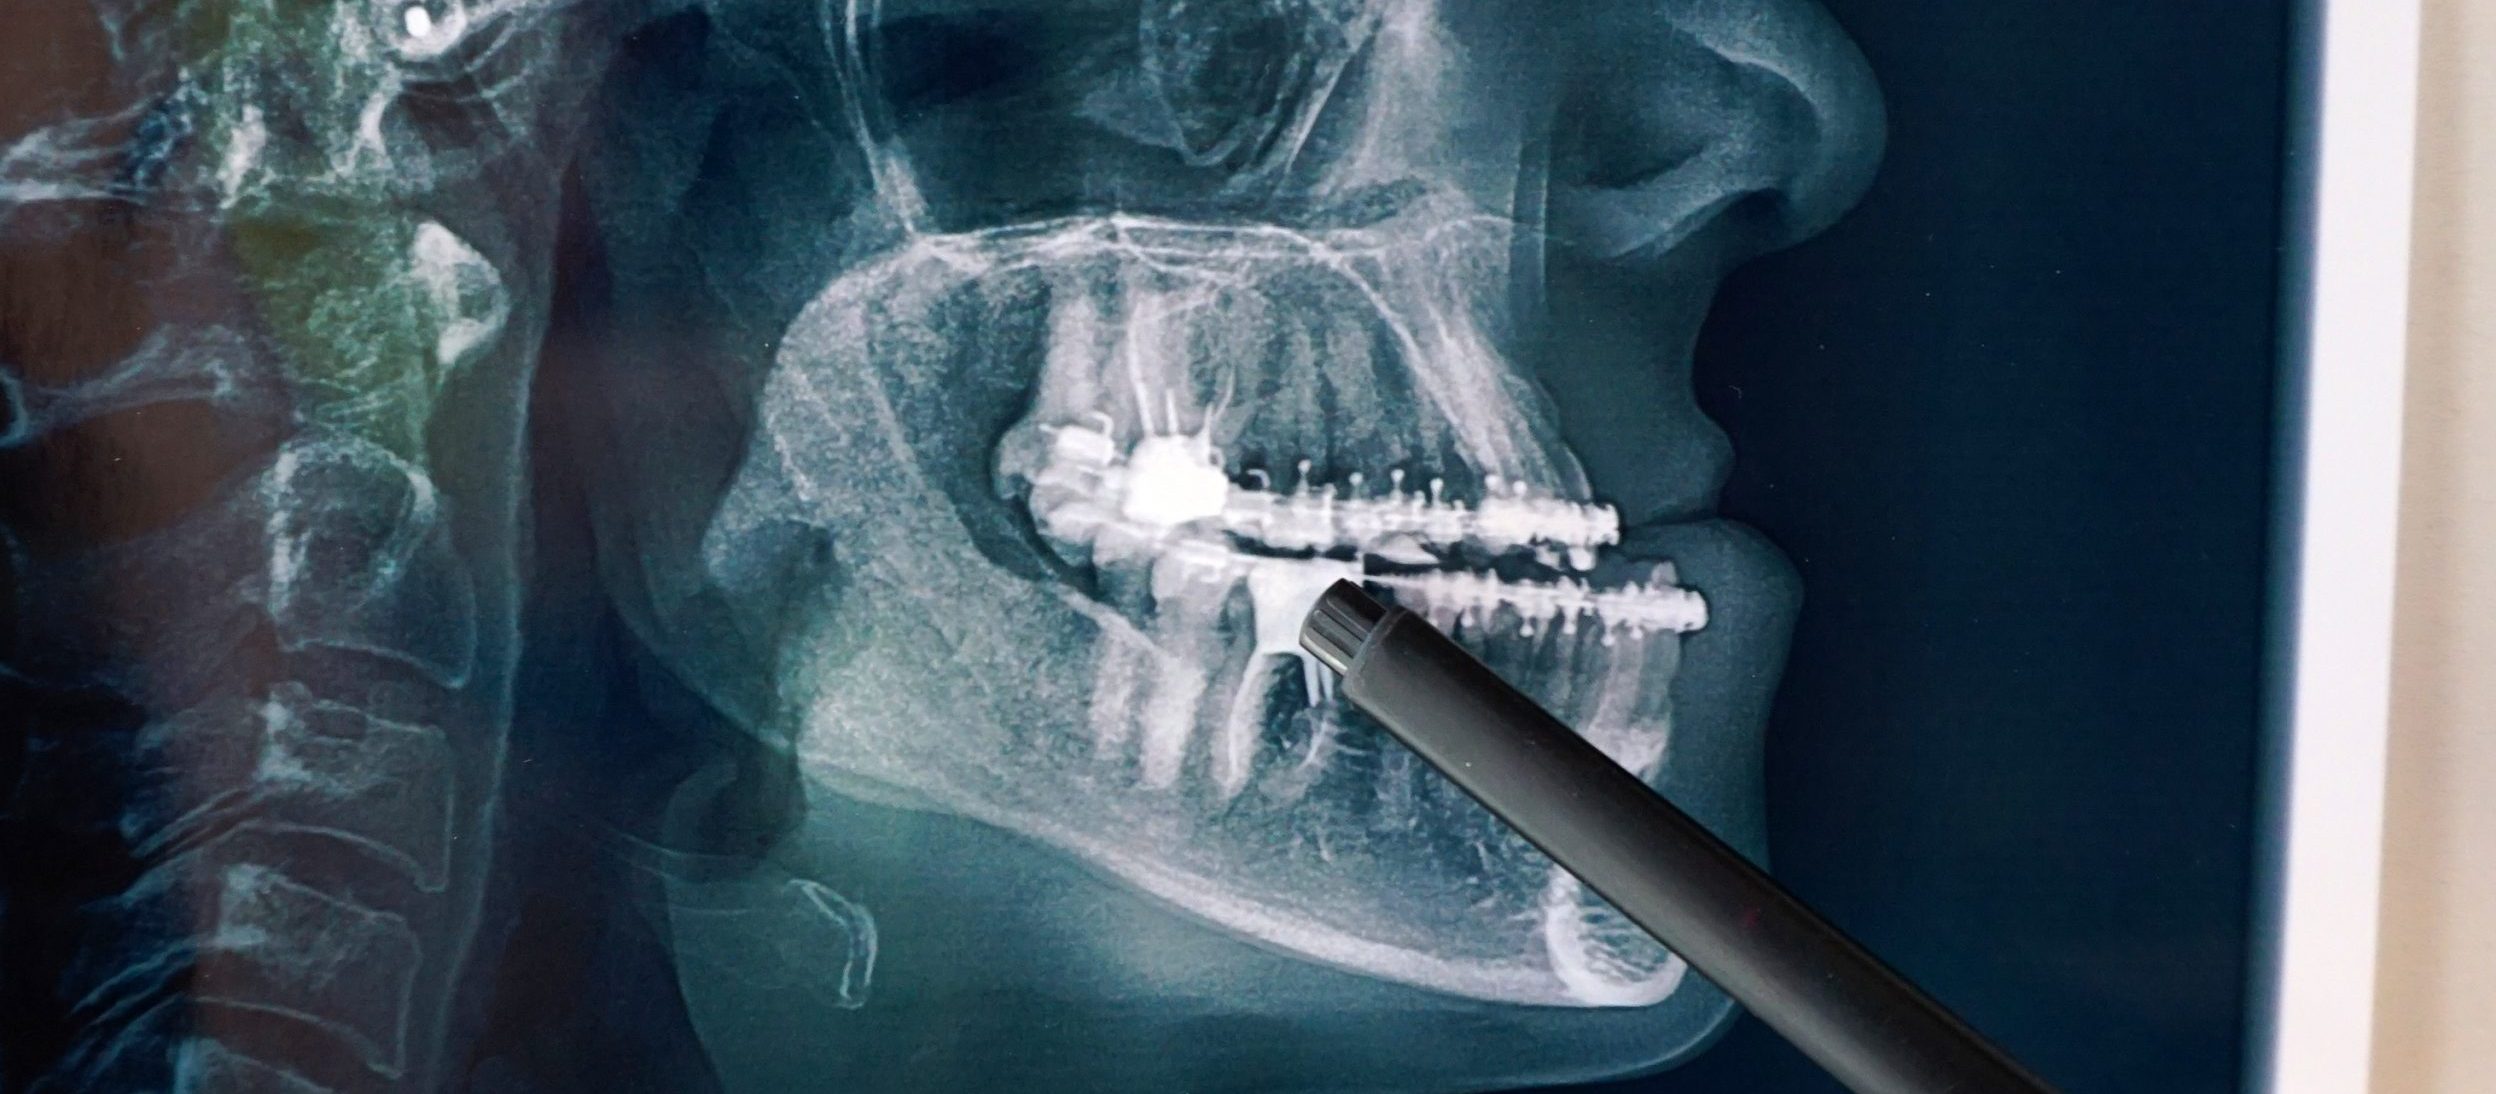

Es importante acudir a un odontólogo al menos una vez al año, para que nos valore y nos indique si debemos visitar a un cirujano maxilofacial. El odontólogo está capacitado para observar mediante el estudio clínico y radiográfico cualquier alteración o si presentamos alguna patología en sí.